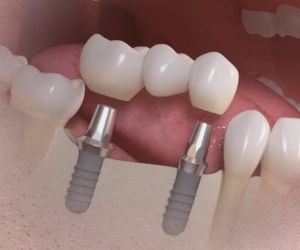

A evolução das técnicas de implantes dentários tem sido notável nos últimos anos, e uma das inovações mais significativas é o enxerto ósseo biomolecular. Este método revolucionário na medicina regenerativa proporciona uma integração mais eficaz entre o implante e o osso do paciente…